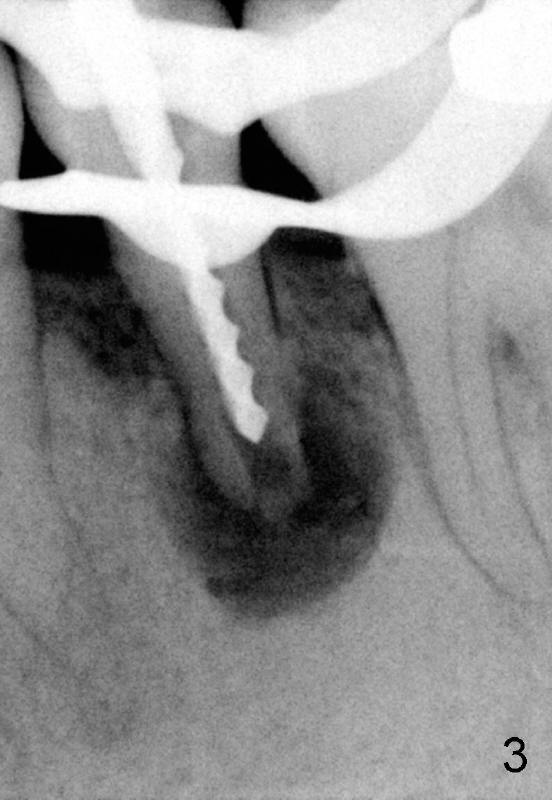

A 40-year-old Chinese man has periodic (once a month) mild pain and swelling in the lower left quadrant. Clinical exam reveals dens evaginatus (Fgi.1': <) in #20. Upon pressure from mouth mirror handle, there is limited amount of purulent discharge from the fistula (Fig.1": <). Preop PA shows a large canal with large periapical radiolucency (Fig.1). RCT started on Aug 6, 2010 with #70 file at 20 mm (Fig.2), #120 file at 16 mm (Fig.3) and CaOH paste in the canal (Fig.4). The dressing changed on Oct 8, 2010 (Fig.5). RCT finished on Jan 25, 2011 with master cone (rolled with several gutta perchae) (Fig.6), lateral condensation (Fig.7) and after vertical condensation and build-up (Fig.8). The canal was wet in the last two appointments with no sign of apexification. Follow up is done in 7 months (Fig.9), 11 months (Fig.10) and 18 months. Although the patient reports no pain after the treatment, the fistula remains with purulent discharge. The patient does not accept apical surgery. What should we do? Retreat with MTA (1,2,3)?